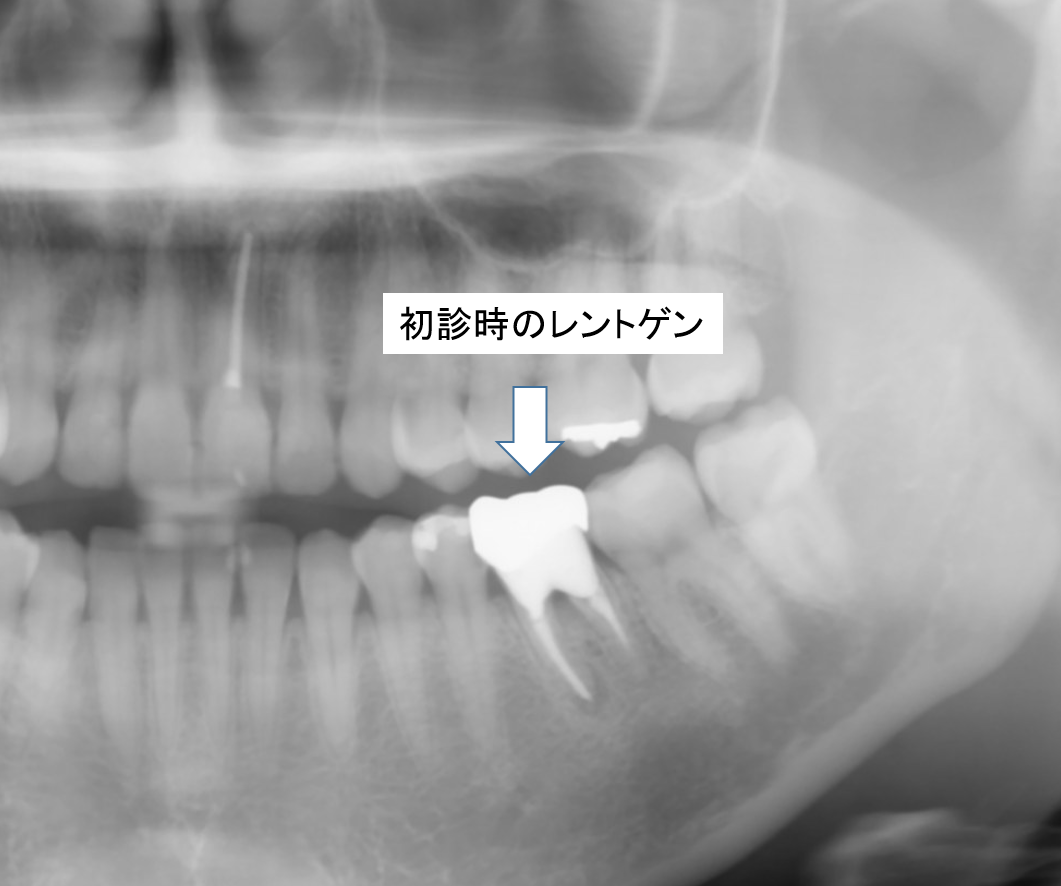

左下の奥歯に違和感、痛みの症状があり、来院されました。

初診時

詳しく検査した結果、2次虫歯による歯質の崩壊および根尖病巣、中程度以上の歯周病(分岐部病変あり)が併発しており、保存が厳しい状況でした。